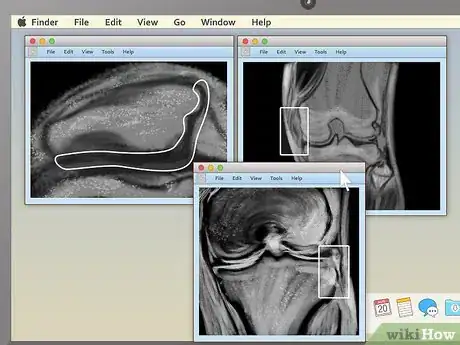

3Pick an appealing series layout. MRI programs almost always have the ability to display more than one image at once. This makes it convenient for doctors to compare different views of the same area or even MRIs taken at different times. For most non-doctors, it's easiest to simply choose a one-image-at-a-time layout and cycle through the images individually. However, there should be onscreen instructions to show two, four, or many more images at once, so feel free to play around with this feature.

4For knee MRIs, look for inconsistencies between the two knees. Comparing coronal views of an injured knee with those of a healthy knee can make it easy to spot problems. A few of the issues you may want to look out for include:[7]

- Osteoarthritis: Decreased joint space in the affected knee. Formation of osteophytes (jagged boney projections the form off the side of the affected knee).[8]

- Ligament tear: Increased joint space in the affected knee. Pocket may fill with fluid that shows up as white or light-colored. Separation of the ligament itself may be visible.[9]

- Meniscus tear: Abnormal joint spacing. Dark-colored features on either side of the joint space pointing inward.[10]